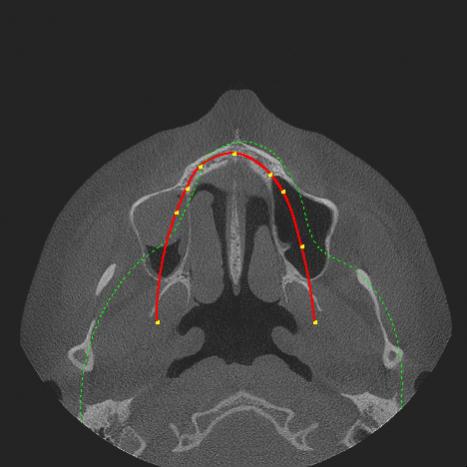

Nach immer weiteren Beschwerden wechselte ich den Kieferchiruge, da ich einen starken Druck auf dem rechten Oberkiefer hatte der in das Gesicht ausstrahlte. OP des neuen Chirurgen, nach Aufklärungsgespräch, war am 5. Januar indem eine ca 1.5-2cm große Fensterung über 16 angelegt wurde, da eine entzundene Kieferhöhlenzyste festgestellt wurde. Nach pathologischem Bericht, den ich auch erhalten habe, war die Zyste 3cm groß und eine mäßig-gradige Entzündung der Kieferhöhle. Der Chirurg meinte es könne Monate dauern zur vollständigen Heilung und bei mir wurde jetzt auch schon viel herumgeschnitten. Nach 5 Wochen habe ich mich nochmals vorgestellt da der Druck/Brennen noch anhält besonderes gegen Nachmittag/Abend und auch teilweise richtig stark wird. Vor der OP konnte ich kaum an meinen Knochen/Zahnfleisch über den Zähnen fassen, da der Bereich wegen der Entzündung geschmerzt hat, nun ist das ohne Probleme möglich. Er meinte ich solle mir keine Gedanken machen er habe einige Patienten die gerade nach solchen chronischen langwierigen Entzündungen rückläufige Beschwerden haben bis zu 3-6 Monate, und meine Entzündung war nicht ohne. Nun sind 7 Wochen vergangen und wenn ich mein Gesicht ruhig halte schmerzt es immer noch mittelstark. Ich weiß die Schmerzen können von mehreren Faktoren kommen und es gibt auch Trigeminus, atypisch, Muskel usw was er erstmal alles ausschließt. Muskel schmerzt nicht beim hindrücken und die Entzündung war ja wirklich da. Lymphknoten sind auch komplett abgeschwollen (die waren 10 Wochen dick). Was sagen Sie abgesehen von anderen Diagnosen, die noch sein könnten, “darf” das nach 7 Wochen noch mittelstark schmerzen (Von dieser OP und Entzündung)? Ich weiß Schmerz empfindet jeder anders und man kann darüber eig keine Aussage treffen daher das “darf”. Anbei ein DVT Screenshot von dem 2ten Chirurgen vor der OP, davor wurde schon eine 1,2cm Zyste über Zahn 17 entfernt. Meinem aktuellen Chirurgen vertraue ich eig. sehr, ich wollte nur nochmals eine zweite Meinung.

[ATTACH=CONFIG]1459[/ATTACH][ATTACH=CONFIG]1460[/ATTACH]

Vielleicht hatten Sie eine nicht dentogene Sinusitis und nun eine iatrogene Sinusitis – also vom Arzt verursacht … senden Sie mir lieber das Bild, welches als Entscheidungsgrund galt für die OP.